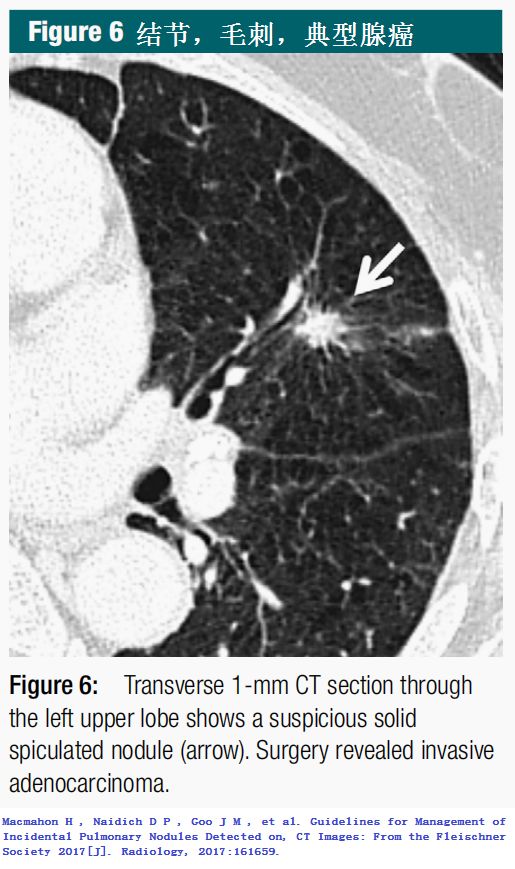

下面这种病灶,一般都是肺癌,尽早手术切除!

(图片点击均可放大)

2.Macmahon H , Naidich D P , Goo J M , et al. Guidelines for Management of Incidental Pulmonary Nodules Detected on, CT Images: From the Fleischner Society 2017[J]. Radiology, 2017:161659.